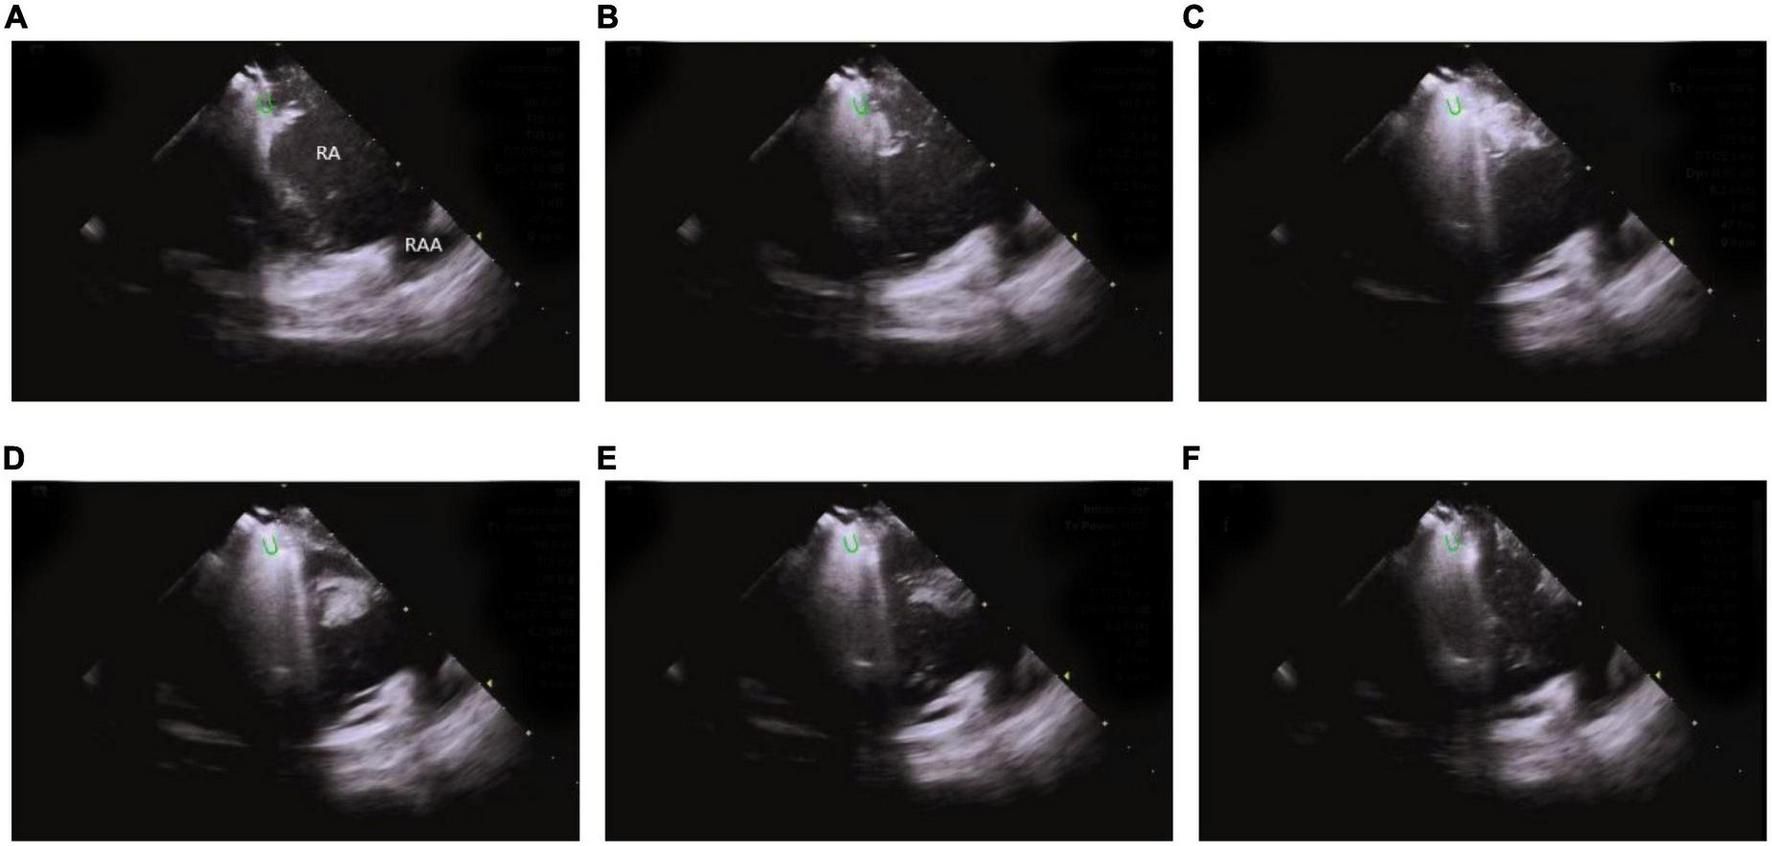

ICE monitors the stability of catheter-tissue contact and the formation of lesions, thus, providing operators with key information to avoid steam popping and myocardial perforations. Any other signs of excessive tissue temperature, such as a local increase in cardiac echoes (excessive whitening of the catheter tip and adjacent cardiac tissue) or a sudden increase of microbubbles (signs before steam popping), can also be successfully detected (60) (Figure 13 and Supplementary Video 2).

FIGURE 13

Steam-pop formation during RF (A–F). (A,B) The microbubbles were observed before steam pop; (C–F) ICE imaging showed that the formation suddenly expanded to a sphere over the course of several seconds. Green semi-ellipse: the positions of the ablation catheter tip; RA, right atrial; RV, right ventricle; RAA, right atrial appendage.

This technique also keeps track of valve changes before, during, and after the surgery, along with complications such as valvular regurgitation caused by valvular insufficiency and rupture of chordae tendineae.